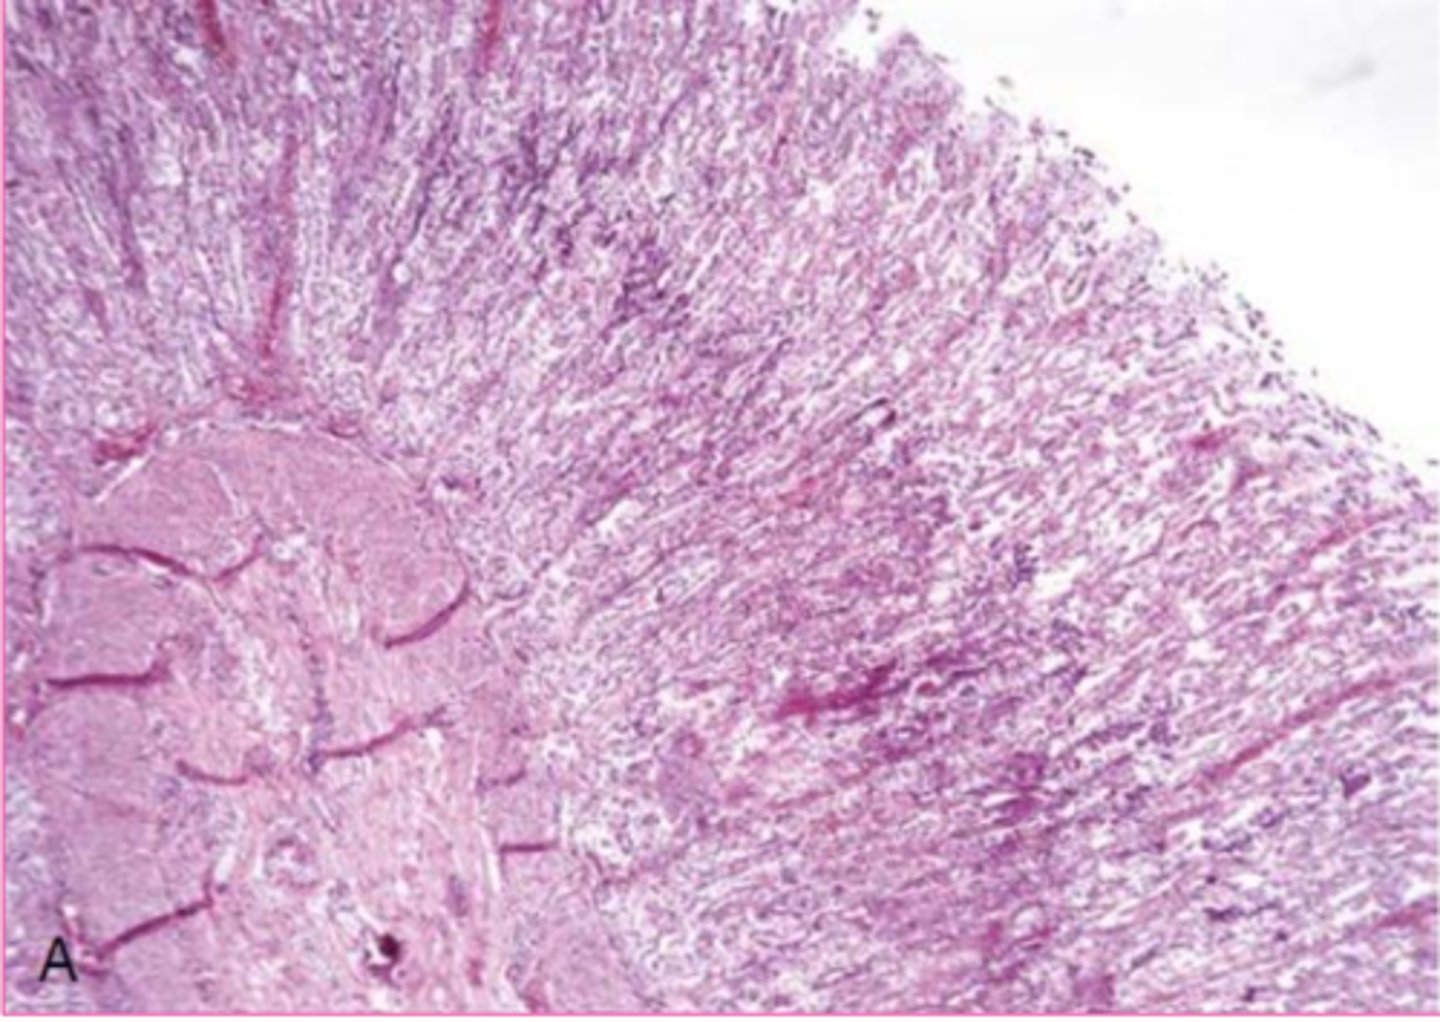

New cards

Dural ossification

What is this extracellular inclusion of the dura mater?

<p>What is this extracellular inclusion of the dura mater?</p>

heterotropic ossification

______________: formation of bony tissue at an extra-skeletal site

in chronic lesions of soft tissue calcification

Where do you find Heterotropic ossification?